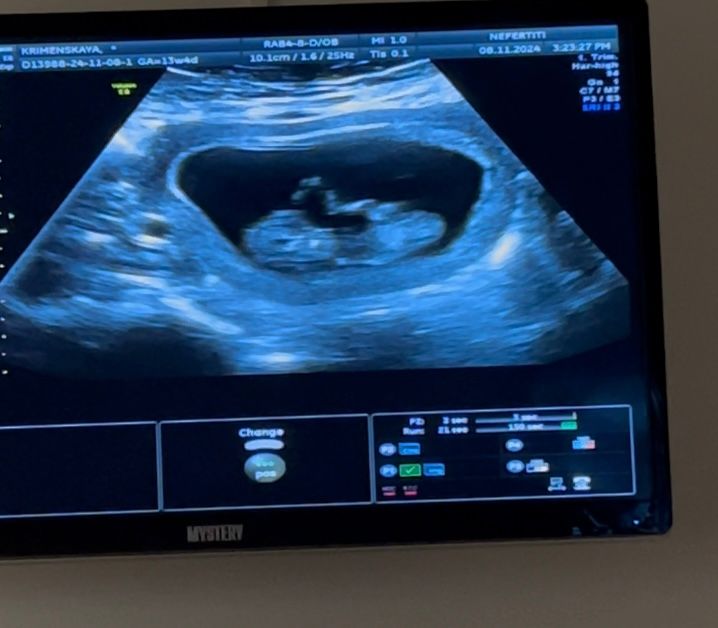

жду мальчика, 13 неделя Москва

УЗИ 9 недель и 2 дня

Ирина , а уже через 2 недели у вас будет так 😁 Изображение

Оля, за 3 недели просто очень вырос, ручки-ножки все видно)

такие они головастенькие поначалу))